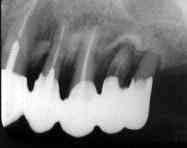

術前5年10ヵ月 「345

術直前(1987.4) 「234

術直後

術後3年

その後

術後9年目に根尖病巣と二次カリエスのため再治療。 決して良好な状態ではないが、手術の意義は十分あったと思われる。

術後9年(1996.6)

術後10年(1997.3)